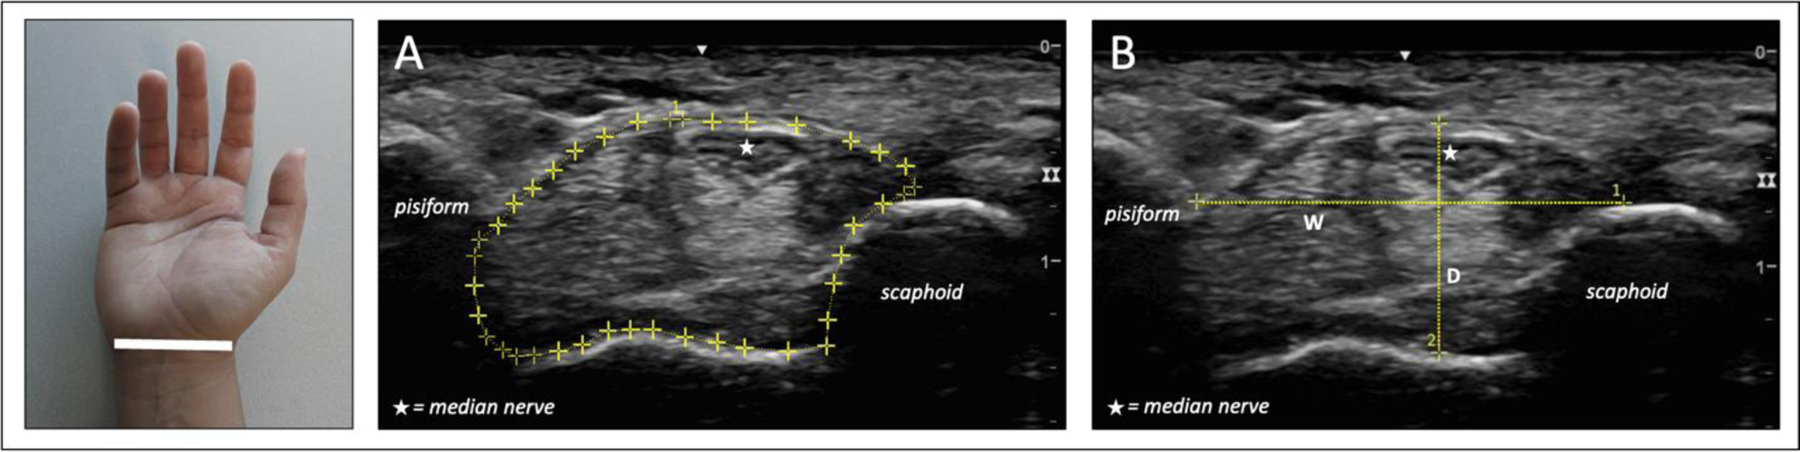

Description:Carpal tunnel syndrome (CTS) is highly prevalent, resulting in decreased function and increased need for costly healthcare services. External wrist ratio (depth/width >0.70) is a strong predictor of the development of CTS and has been suggested to be a proxy for internal carpal tunnel (CT) shape. Conversely, sonography can more directly evaluate CT shape. The purpose of our study was to explore the relationship between wrist ratio and sonographic CT measurements to (1) evaluate the reliability of sonographic CT measurements and (2) explore how external wrist measures relate to anthropometric features of the CT. We used sonographic imaging on a sample of healthy participants (n = 226) to measure CT cross-sectional area, depth, width, and depth/width ratio. We conducted exploratory correlation and regression analyses to identify relationships of these measures with external wrist ratio. Reliability for dominant and nondominant sonographic CT measures ranged from good to excellent (0.79-0.95). Despite a moderate correlation between CT width and depth and their external wrist counterparts (0.33-0.41, p < 0.001), wrist ratio and CT ratio demonstrated weak to no correlation (dominant: r = 0.12, p = 0.053; nondominant: r = 0.20, p = 0.002) and the mean CT ratio was far lower than the mean wrist ratio (0.45 vs. 0.71 bilaterally). Supporting this, we observed several key differences in the relationship between external wrist measures compared to corresponding CT measures. Additionally, regression analyses combining participant factors and CT measurements produced models accounting for less than 15% of the variability in external wrist ratio (linear models) or correctly predicting less than 68% of wrist ratio-based risk categorization (logistic models). Overall, among healthy young adults, wrist shape is not an adequate proxy for CT shape.